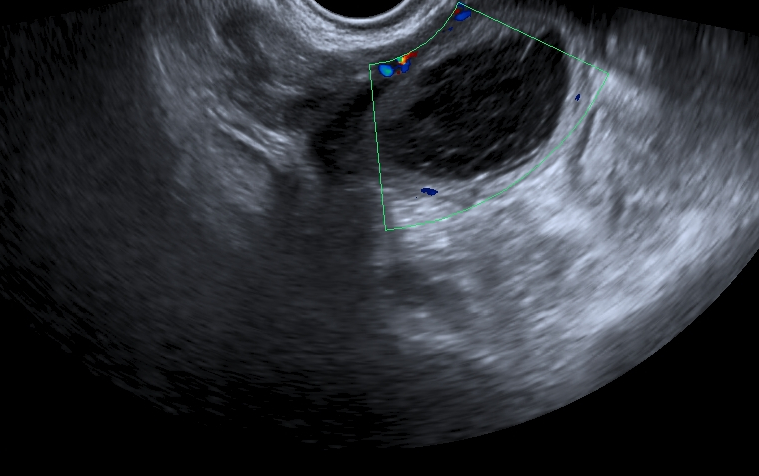

La principal consecuencia a corto plazo para la mujer cuando desarrolla una endometriosis es la aparición de un fuerte dolor abdominal. Lo primero que hay que hacer, en caso de notar este síntoma, es consultar al especialista. Una simple ecografía puede servir para detectarla y dar detalles a tu médico sobre el tipo de dolor que sientes, cuándo aparece, si hace muchos años que lo sufres, etc. Se trata, en definitiva, de una información muy valiosa que puede acelerar el diagnóstico y, por tanto, la curación.